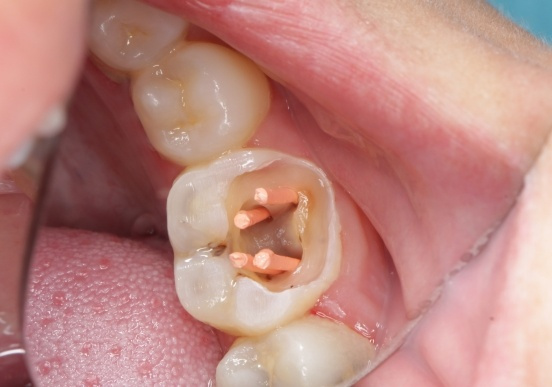

什么是显微根管治疗 根管治疗后为何要用牙冠修复 根管治疗,俗称“杀神经”,是现有治疗牙髓炎和根尖周炎的首选方法。显微根管治疗是借助手术显微镜和显微器械在放大的视野和聚焦的照明下进行根管治疗的方法,手术显微镜和... 根管治疗 厉涵山 591 2023-11-09

根管治疗的治疗过程是什么样的 牙齿根管治疗术的过程是医生用牙齿根管治疗专用的器械通过彻底去除感染的牙髓以及感染的牙本质和毒性分解产物,严密填塞根管,隔绝细菌进入根管再感染,防止根尖周病变的发... 根管治疗 巨伟懋 510 2023-11-11

什么叫根管治疗 根管治疗的过程是什么样的 根管治疗是牙科常用的一种治疗技术。治疗中,医师使用根管治疗的专用器械,通过彻底去除感染的牙髓以及感染的牙本质和毒性分解产物,严密填塞根管,隔绝细菌进入根管,避免... 根管治疗 范姜英杰 508 2023-10-28